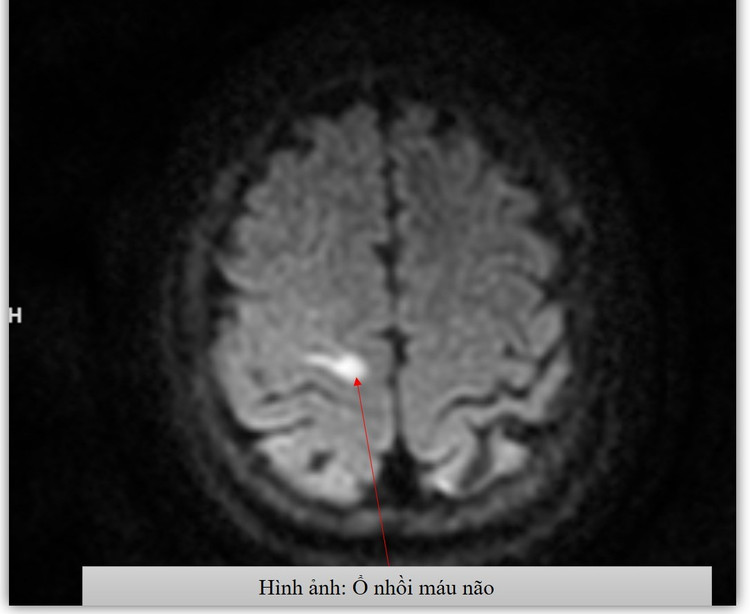

Kết quả chụp MRI và chụp mạch máu não (DSA) cho thấy bệnh nhân bị nhồi máu não cấp vùng vỏ não, liên quan đến hẹp tắc động mạch não giữa hai bên – đặc trưng của bệnh Moyamoya.

Kết quả chụp MRI - Ảnh BVCC